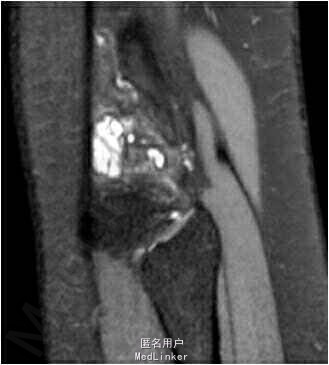

查体:双下肢无畸形,右膝关节关节间隙压痛,麦氏征(+),肢端血运、感觉、活动正常。左下肢及双上肢其余关节未见明显异常。MRI检查提示:右膝关节半月板损伤伴囊肿形成。

诊断:右膝外侧半月板后角损伤伴囊肿形成。拟行手术:右膝关节镜检,囊肿清理,半月板修补。

该部位的囊肿接近腘窝,腘窝处有重要的神经血管,请问在关节镜手术技巧上要注意什么?